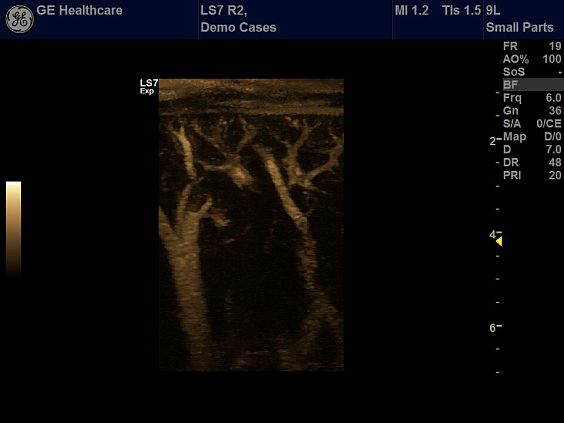

Клинические изображения

- B-Flow / Color B-Flow - режим недопплеровской визуализации кровотока

- LS7 HiRez Contrast - режим кодированной контрастной гармоники для проведения исследований с контрастными веществами с повышенным разрешением

Ультразвуковой аппарат LOGIQ S7 XDclear предназначен для использования специалистами из различных областей диагностики. Его расширенный функционал включает такие возможности как B-Flow — недопплеровская технология отображения кровотока в B-режиме, компрессионная эластография (качественная и полуколичественная), количественный анализ васкуляризации, функцию В-Steer+ — изменение угла наклона УЗ луча в B-режиме, 3D/4D диагностику и мультимодальную визуализацию.